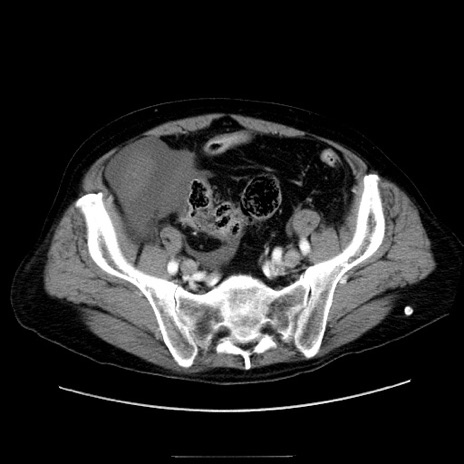

症例30(横断像)

【症例】80歳代男性

【主訴】臍周囲痛

【現病歴】約6時間前から臍下部痛が出現。次第に腹部膨隆・背部痛も生じてきたため来院。背部痛の場所は変化しない。

【既往歴】腎盂腎炎

【身体所見】意識清明、BT 36.3℃、BP  131/87mmHg、P 87bpm、SpO2 100%(RA)、臍周囲自発痛・圧痛あり、反跳痛なし、自発痛部位に一致して板状硬あり、腹部膨隆、腸雑音減弱、CVA tenderness両側陰性。

【データ】WBC 19600、CRP 0.33